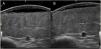

An 8-year-old girl was referred from the emergency department for evaluation of a painful lesion on the left leg that had appeared several weeks earlier after a fall from a ladder. Physical examination revealed a subcutaneous bulge of about 4cm in diameter in the left pretibial region with yellowish-purpuric overlying skin and a strikingly gummy consistency. The patient had reticulated erythematous-violaceous lesions on the right leg and dehiscent and atrophic scars on the right leg and left knee (Fig. 1). High-frequency ultrasound (18 MHz) of the left pretibial lesion revealed an anechogenic collection delimited by a thin pseudocapsule, compatible with an organized hematoma (Fig. 2A). Septal edema compatible with traumatic panniculitis was evident in the surrounding hyperechogenic subcutaneous tissue. Doppler signal was absent. In the directed anamnesis the patient's mother reported that the girl had been born preterm due to premature rupture of membranes and had muscular hypotonia during the neonatal period. The patient was undergoing tests in the endocrinology department of another hospital for short stature and disproportion between the trunk and limbs. The family history provided by the mother included joint hyperlaxity, abnormal scarring, and early osteoarthritis. The patient also presented with skin hyperextensibility, joint hypermobility, and Gorlin sign (ability to reach the nose with the tip of the tongue) (Fig. 3). Based on these data a suspected diagnosis of classic EDS was established. A cardiological examination, including electrocardiogram and echocardiography, revealed no findings of interest, and the results of a laboratory workup, including a complete blood count and coagulation tests, were normal apart from slightly elevated D-dimer levels. A second ultrasound examination performed 1 month later revealed a reduction in the hematoma of approximately 50% (Fig. 2B).

High-resolution ultrasound is a useful tool for diagnostic confirmation of bruising and differentiation from other causes of subcutaneous lesions on the legs, including erythema nodosum, abscesses, and benign (lipoma) or malignant (rhabdomyosarcoma, fibrosarcoma) soft-tissue tumors.6 Hematomas present as anechoic collections that may become hypoechoic or heterogeneous over days or weeks, without peripheral hypervascularization. These lesions can be compressed with the ultrasound probe only in early stages, after which the fluid within is replaced with fibrous tissue. Another feature, which is less well characterized in the literature, is the presence of a thin pseudocapsule that corresponds to the fibrin and peripheral granulation tissue produced as the hematoma organizes. In contrast to hematomas, the aforementioned subcutaneous lesions tend to have more irregular borders and usually differ in terms of the degree of vascularization. Ultrasound also allows measurement of the depth of the hematoma and confirmation of its regression, allowing distinction from hemorrhagic soft-tissue tumors.6